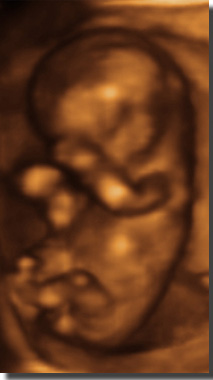

Live 3/4 D Ultraschall

30.

SSW